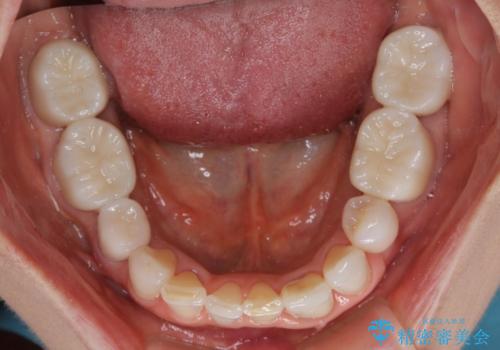

奥歯の目立つ銀歯をセラミックに オールセラミッククラウン治療